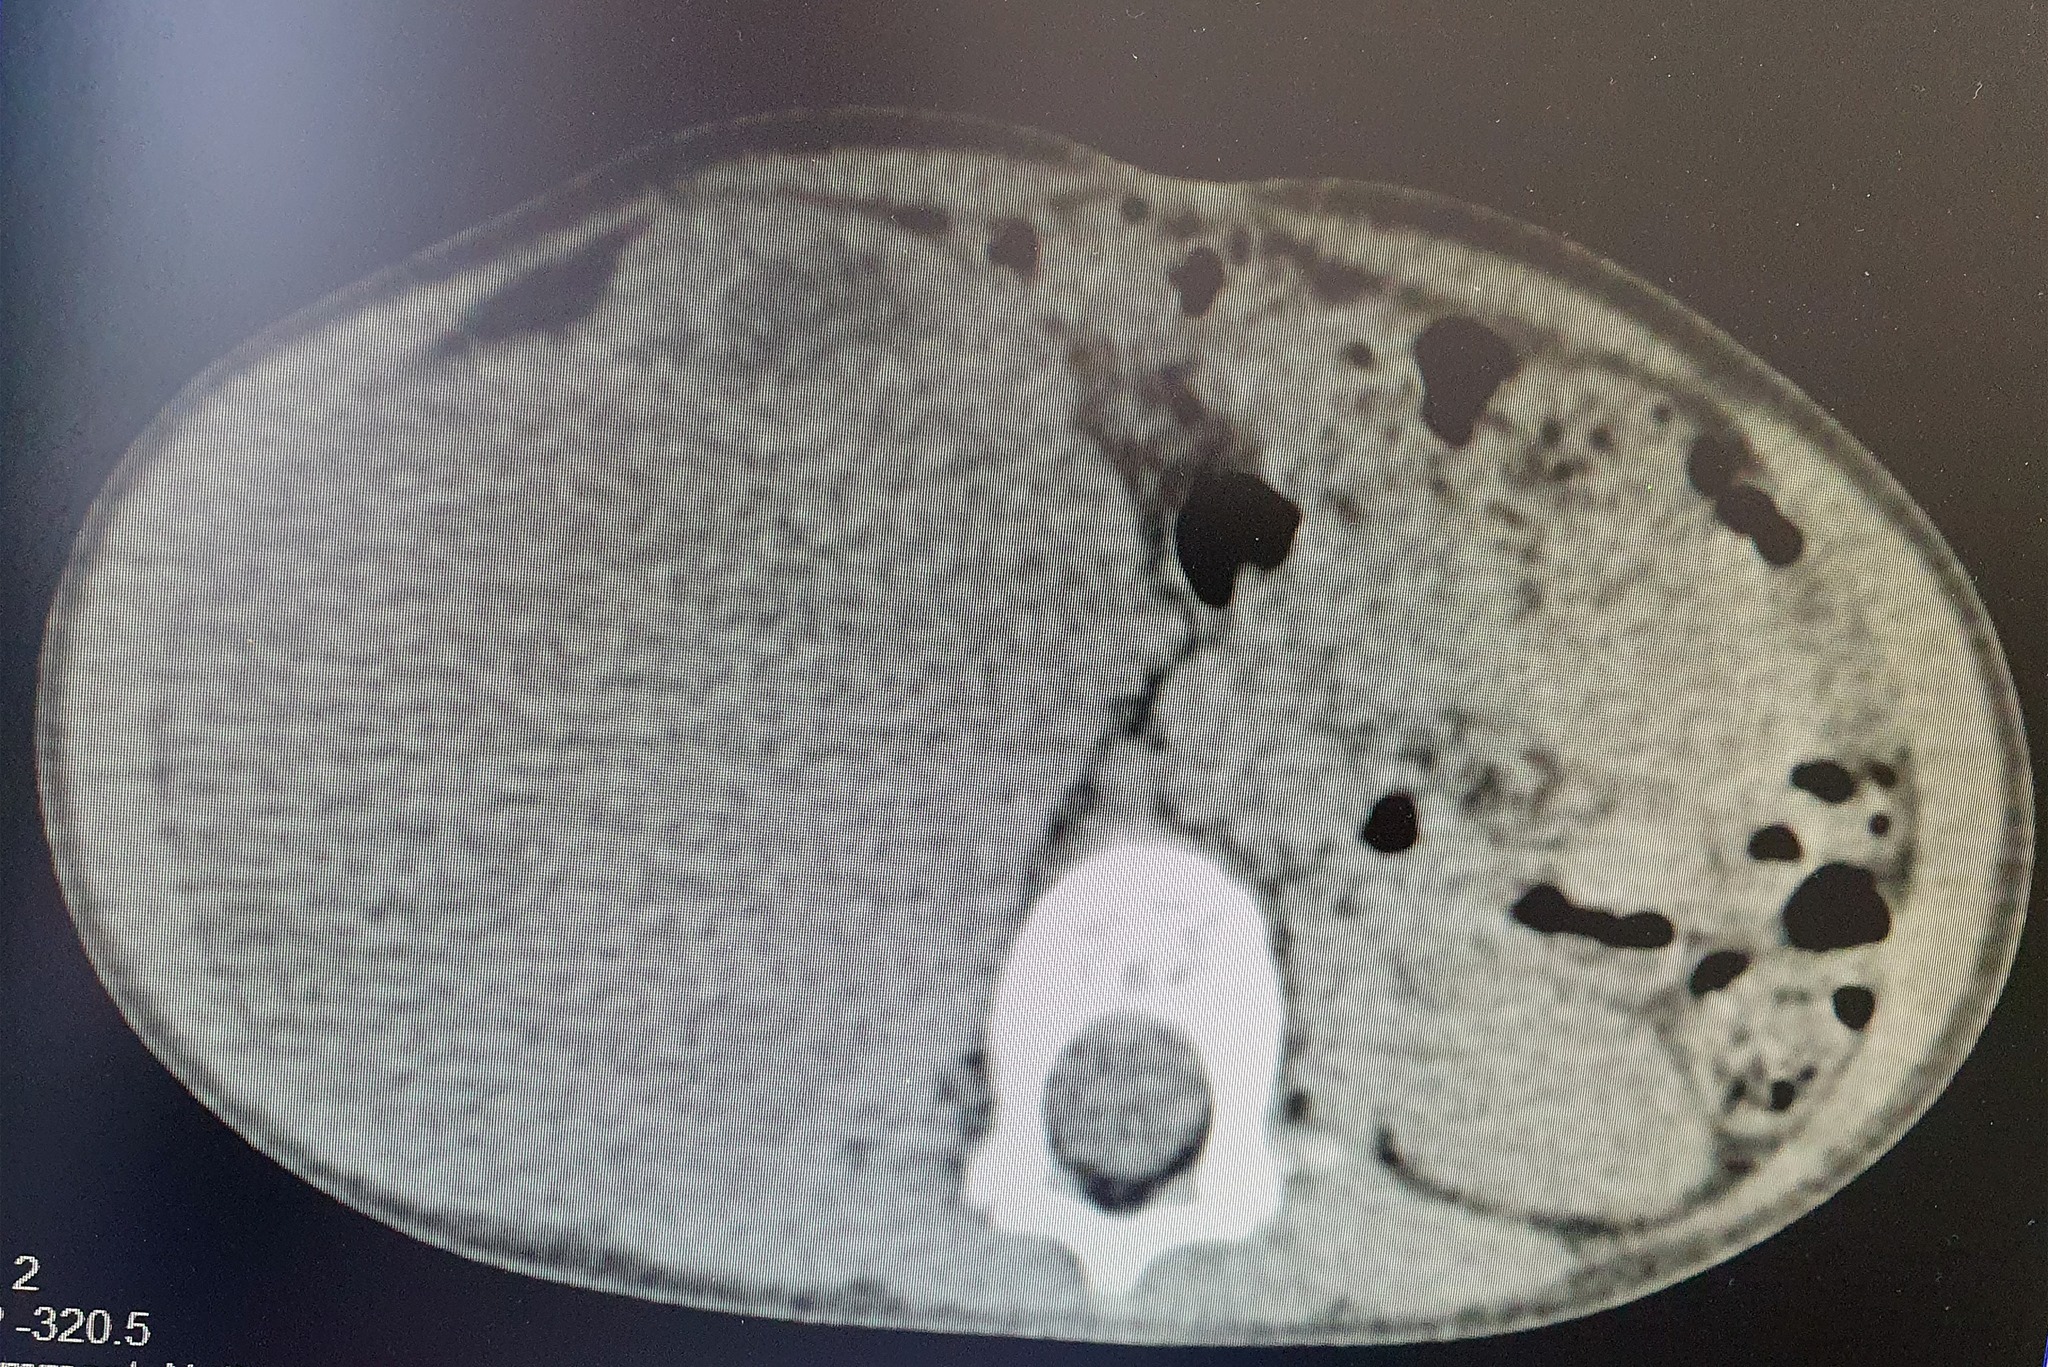

Shërbimi Spitalor Klinik dhe Universitar i Kosovës përmes një postimi në rrjetin social “Facebook” kanë treguar se sot i është operuar me sukses një fëmijë 2 vjeç, të cilit i është hequr tumori me përmasa të mëdha.Ata kanë njoftuar se mjekët kirurgë, të asistuar nga ekipi i anestezionit kanë operuar me sukses një fëmijë të moshës 2-vjeçare, duke ia larguar tumorin, i cili ia kishte përfshirë gjysmën e barkut.

Operacion i rrallë në QKUK: 2-vjeçarit i hiqet tumori me përmasa të mëdha